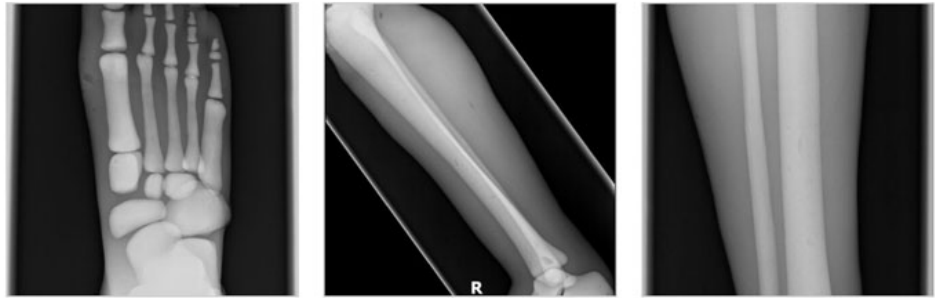

成人腿部模體,用于 X 射線 CT 和超聲波的成人腿部(肌肉)模型是一種基于人類(lèi)男性腿部平均解剖結(jié)構(gòu)設(shè)計(jì)的逼真模型。它具有所有基本的骨骼和

軟組織特征,使其成為學(xué)習(xí)、研究和測(cè)試醫(yī)學(xué)成像設(shè)備的理想工具。 模體可用于研究不同方向和定位技術(shù)的多種診斷性 X 射線 CT 和超聲程序。根據(jù)

要求,該產(chǎn)品可以根據(jù)不同的病理進(jìn)行定制,也可以用于特定的培訓(xùn)應(yīng)用。 模體尺寸:965.2 x 254 x 177.8 毫米,重量:12kg(約)